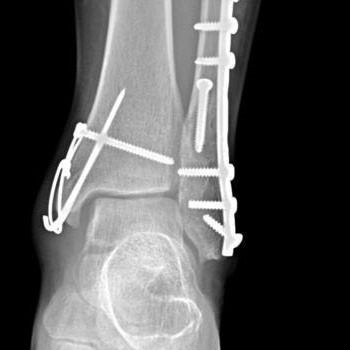

Fractura tratata de dr Chitea Claudiu Daniel